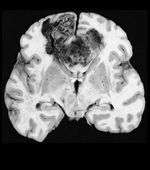

Untreated glioblastoma multiforme with the classic "butterfly" configuration

Glioblastoma multiforme is the most prevalent type of primary malignant brain tumor. It is associated with a poor prognosis-the 5-year survival rate is approximately 4.5%. Overall, more than 22,000 malignant brain and spinal cord tumors were diagnosed in 2010 according to the American Cancer Society. Glioblastoma multiforme tumors are diagnosed in 17,000 patients every year. No standard of care exists for patients with recurrent glioblastoma. Primary treatment is radiotherapy and temozolomide after surgical resection. The treatment prolongs survival but most patients progress within about 7 months.